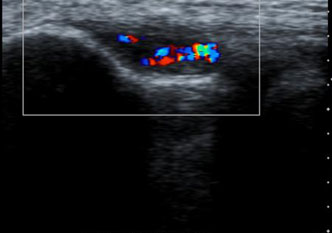

eco-aumento vascolarizzazione

• Ecografia: può mostrare cambiamenti strutturali che interessano i tendini (come ad esempio ispessimento, assottigliamento, aree degenerative, lesioni e/o calcificazioni, grado di vascolarizzazione dei tessuti).